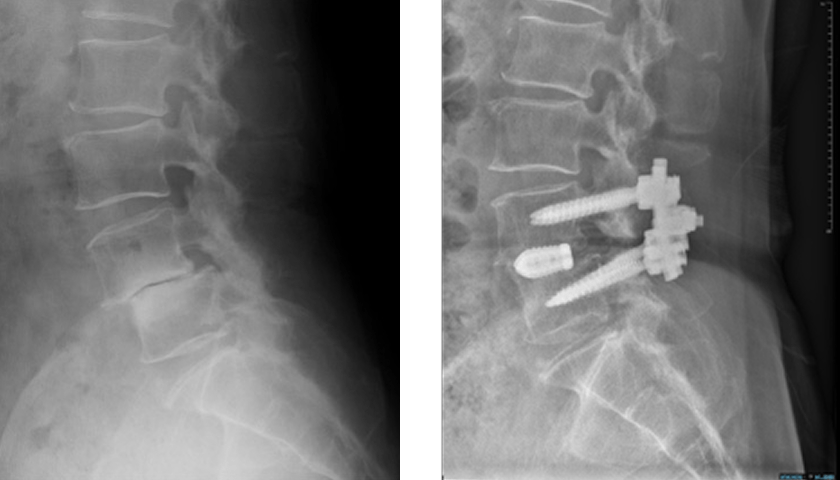

軽症ではコルセットやリハビリ、薬物療法で経過観察。神経圧迫が強い場合は、以下の手術を行います。

後方除圧固定術(PLIF/TLIF)

神経除圧と同時にスクリューで安定化

当院では低侵襲(MIS)手術を積極的に導入し、早期離床・短期入院を実現しています。

治療